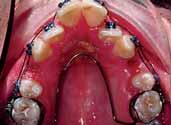

3. Anterior bite plan to reduce the overbite and bonding the lower arch (Figure 5).

The oral hygiene of the patient and the carious lesions were addressed prior to the start of the fixed appliances treatment. The patient’s compliance was good and treatment progressed without encountering major problems. The reduction of the overbite was achieved initially with the anterior bite plane then a reverse curve of Spee was placed in the lower archwire to control the overbite. A Trans-Palatal Arch (TPA) with Nance button was fitted prior to the extraction of the upper premolars in order to reinforce the anchorage (Figure 6). The treatment continued with the use of Class II traction on both sides and space closure mechanics.

The treatment of the case was planned in stages. Stage one consistedof improving the oral hygiene of the patient and management of all carious lesions and assesses the compliance and attitude of the patient towards orthodontic treatment. The next stage involved the reduction of the overbite. The patient presented with a deep overbite that was causing damage to the palatal mucosa (Figure 2). This was achieved with an anterior bite plane removable appliance and bonding of the lower arch. This appliance will free the occlusion of the buccal segment teeth and if worn consistently, will “passively” limit further eruption of the incisors but allow the lower premolars to erupt, thus reduce the increased overbite (Figure 5).

The next phase of treatment involved the fitting of the Trans-Palatal Arch (TPA) and the removal of the upper first premolars. Because of the increased overjet, this was a case of maximum anchorage and any mesial movement of the upper buccal segments was not desirable (Figure 6). It remains equivocal in the literature whether TPA appliances can provide anteroposterior anchorage. In fact, recent evidence suggested the contradictory 8 Alternatively the anchorage issue in this case could have been addressed with a Temporary Anchorage Device. The increase